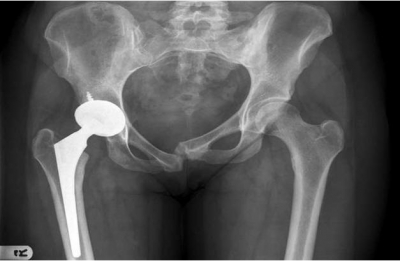

耻骨联合分离过大:会出现跨部增宽。耻骨联合分离过大,会出现跨部增宽。

耻骨联合处分离过大